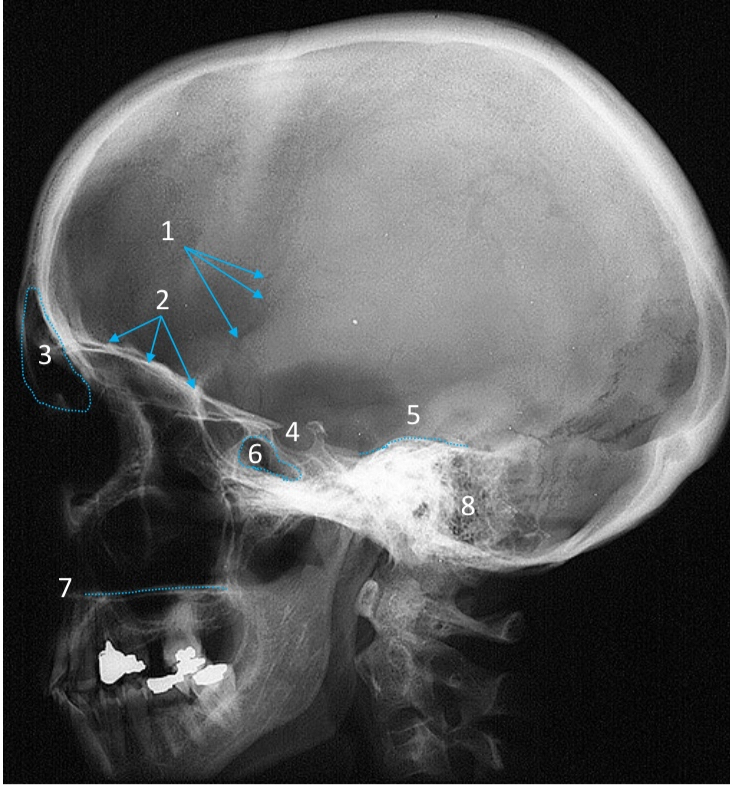

Mandible

ID bone

Maxilla

ID bone

Frontal sinus

ID structure

Pituitary fossa

ID structure

Occipital

ID bone

Lambdoid suture

ID structure

Frontal sinus

ID structure

Orbital margin

Orbit

Maxillary sinus

ID structure

Mandibular condyle

ID structure

Inferior nasal concha

ID structure

Hard palate

ID strucutre

Gonial angle

ID strucutre

Petrous ridge

ID structure

Groove of middle meningeal a.

ID structure

Roof of orbit

ID structure

Frontal sinus

ID structure

Pituitary fossa

ID structure

Petrous ridge

ID structure

Sphenoid sinus

ID structure

Hard palate

ID structure

Mastoid air cells

ID structure

Zygomatic arch

ID structure

Mandibular condyle

ID structure

External auditory meatus

ID structure

Mastoid air cells

ID structure

Foramen magnum

ID structure

Foramen ovale

ID structure

Foramen spinosum

ID structure